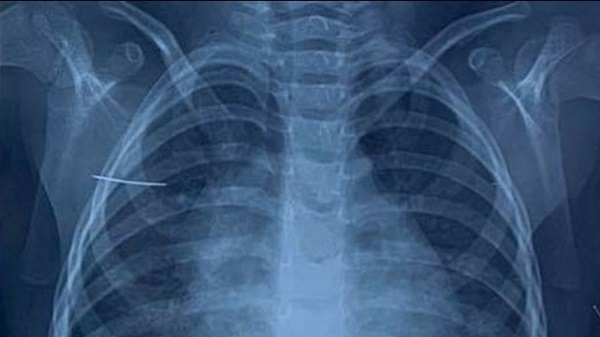

Trên phim chụp X-quang của bệnh nhi. Ảnh do BV cung cấp. |

Theo thông tin tử bệnh viện Nhi Trung ương, ngày 23/4, các bác sĩ Khoa Ngoại tổng hợp đã thực hiện ca mổ nội soi kéo dài 1 giờ, gắp ra từ cơ thể bé gái 3 tuổi một chiếc kim khâu dài khoảng 4 cm.

Gia đình bệnh nhi cho biết, 2 ngày trước khi nhập viện, trong lúc chơi đùa bé gái P.D.C (huyện Bình Giang, tỉnh Hải Dương) vô tình nằm đè vào chiếc kim khâu. Sau tai nạn, bé có biểu hiện đau vùng vai phải nên đã được gia đình đưa đến khám tại bệnh viện tỉnh. Tại đây, các bác sĩ bệnh viện tỉnh đã phát hiện có dị vật ở lồng ngực bên phải của bé, nghi là chiếc kim khâu. Ngay lập tức, cháu được chuyển tới bệnh viện Nhi Trung ương.

Tại bệnh viện Nhi Trung ương, khi tiến hành cho bệnh nhi chụp X-quang và cắt vi tính lồng ngực, các bác sĩ phát hiện dị vật hình kim khâu nằm tại vị trí mặt trước xương bả vai. Cháu C. được chỉ định phẫu thuật để lấy vị vật ra khỏi cơ thể.

Bác sĩ Nguyễn Minh Khôi, khoa Ngoại tổng hợp, người trực tiếp phẫu thuật cho bé C. chia sẻ: “Trong quá trình phẫu thuật nội soi bằng 03 trocar đi vào tổ chức giữa cơ dưới vai và cơ thang, các bác sĩ phát hiện dị vật nằm lẫn trong các sợi cơ là chiếc kim khâu dài 3.8cm, đầu nhọn. Sau 1 giờ, dị vật đã được lấy ra hoàn toàn, không đứt gãy”.

Trong trường hợp của cháu C., dị vật được các bác sĩ xác định chính xác nhờ phim chụp cắt lớp 128 dãy có dựng hình kết hợp phẫu thuật nội soi vào khoang dưới cân nông giúp giảm sang chấn, tổn thương tổ chức và thẩm mỹ sau mổ.